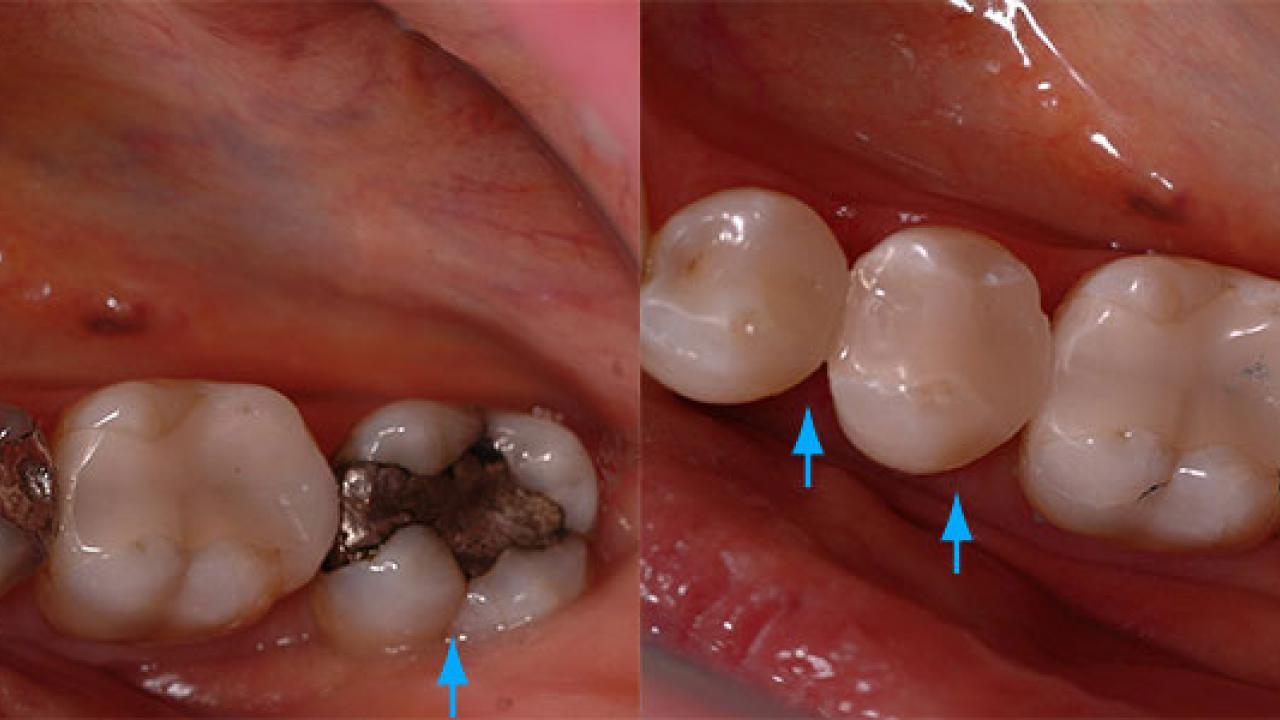

We’d like to let our results do the talking. Check out some of our amazing transformations in our Smile Gallery, combining a mixture of tooth coloured restorations, implant treatments, crowns, veneers, tooth whitening and full mouth rehabilitation.